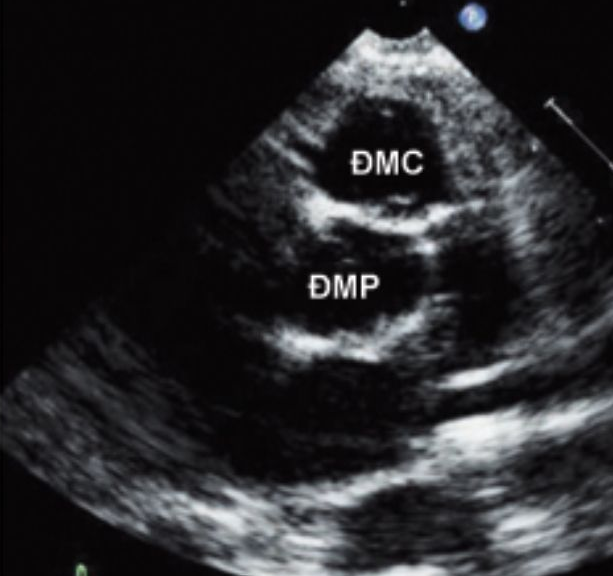

Cùng với đó, là hình ảnh siêu âm tim trên mặt cắt trục dài cạnh ức: Động mạch phổi xuất phát từ thất trái. Động mạch phổi và động mạch chủ không bắt chéo nhau (đi song song) – hình 1 và trên mặt cắt trục ngắn cạnh ức: Động mạch chủ ở phía trước và bên trái động mạch phổi – hình 2

Hình 2